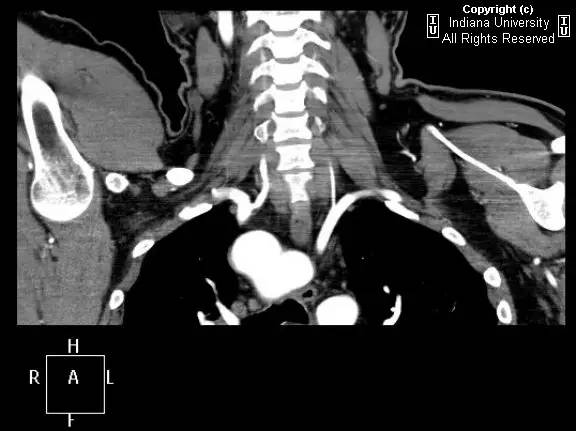

【影像学表现】胸部平片示右位主动脉弓,肺动脉突出,双肺清晰。CT示右位主动脉弓,并右位降主动脉,迷走左锁骨下动脉起自后方,从食管后走形形成血管环。迷走左锁骨下动脉与憩室相关(Kommerell)。食管因左锁骨下动脉及憩室而向前移位。

【诊断】右位主动脉弓并血管环形成、迷走左锁骨下动脉并Kommerell憩室

Right-sided aorticarch, with vascular ring and aberrant left subclavian with Kommerell\’sdiverticulum